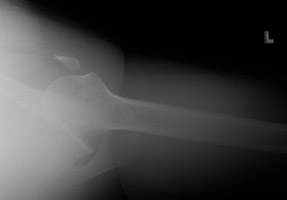

- Click on the image for a larger versionCGrashey radiograph of the left shoulder. This shows the fractured portion of the coracoid process as well as the anterior dislocation of the humeral head.